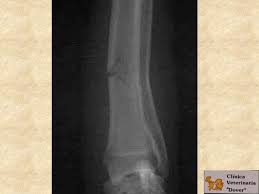

En primer lugar vamos a mencionar las fracturas simples, básicamente estas solo van a tener una línea de fractura, por otro lado las fracturas conminutas tienen más de una línea de fractura y adicionalmente trozos del hueso que sean han separado.

Por lo general y tomando en cuenta el hueso que fue afectado, las fracturas simples se pueden tratar de manera más fácil que las fracturas de conminutas.

De igual forma se encuentran las fracturas incompletas, afectan únicamente un lado del hueso, son dolorosas, sin embargo puede permanecer estable, esto cambia si se convierte en una fractura completa, esto ocurre cuando el hueso, llega a sufrir una fragmentación en dos pedazos.